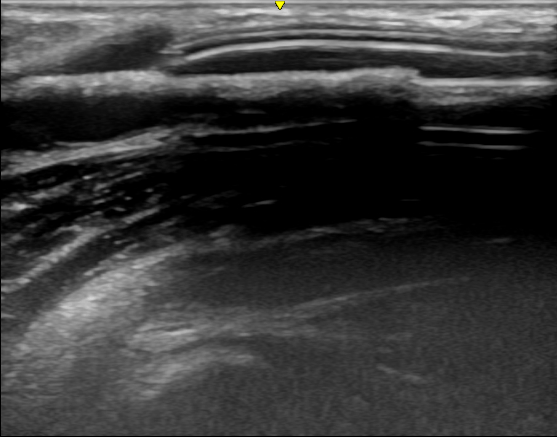

【覆膜|肾脏内科实施陕西省首例超声引导下透析通路支架植入术】近日 , 西安交通大学第一附属医院肾脏内科透析通路团队为一位人工血管内瘘狭窄的患者成功实施了超声引导下覆膜支架植入术 , 这是陕西省首例在超声下进行的此类手术 , 标志着西安交大一附院透析通路介入治疗技术的又一次提升 。 患者为男性 , 55岁 , 诊断为慢性肾炎 , 慢性肾功能衰竭 , 使用左前臂人工血管内瘘规律透析1年 。 该患者此前因为人工血管内瘘狭窄曾接受两次经皮静脉球囊扩张术(PTA) , 但术后狭窄很快复发 , 对于这种狭窄容易复发且单纯PTA效果不佳的患者 , 覆膜支架植入术是比较好的解决方法 。 经过充分的术前准备和一个小时的手术 , 肾脏内科杨世峰副主任医师及其团队成功为该患者实施了超声引导下覆膜支架植入术 , 术后患者人工血管内瘘血流恢复通畅 , 透析过程中血流量充足、静脉压正常 , 达到了较好的手术效果 。

血液透析通路是尿毒症患者的“生命线” , 目前尿毒症患者最常用的透析通路是自体动静脉内瘘和人工血管内瘘 。 然而内瘘无法避免的并发症就是狭窄 , 长期高速的血流会引起血管内膜反应性增生 , 导致内瘘管腔狭窄和血流量不足 , 影响透析效果 , 狭窄严重时导致内瘘闭塞、血栓和失功 。 处理动静脉内瘘狭窄最有效的方法就是PTA , 通过血管腔内治疗的方法解除狭窄 , 具有创伤小、恢复快的优点 。 然而部分病例单纯PTA后狭窄容易短时间内复发 , 对于这些病例覆膜支架植入是较好的解决办法 。 传统的支架植入术是在DSA造影下进行 , 而超声引导下介入手术是近几年新兴的技术 , 超声引导具有方便、无辐射损伤 , 无造影剂损害、可显示闭塞病变等优点 , 特别适合动静脉内瘘等外周血管的介入治疗 。